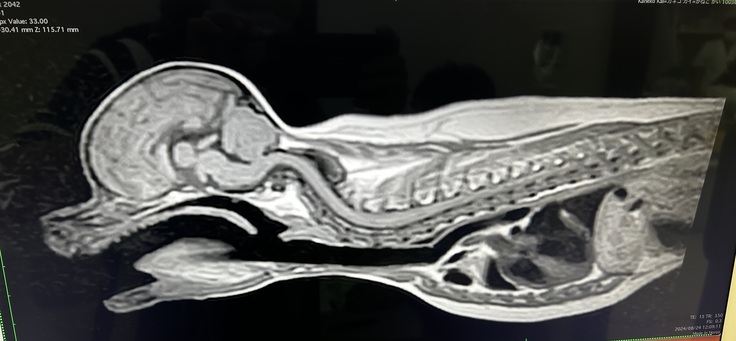

その後も症状は改善せず、レントゲンや超音波の検査をしました。獣医さんに『水頭症か頸椎に問題があるかもしれない。詳しくは大きな病院でMRIやCTを撮らないと分かりません』とのことでした。

詳しい検査のため二次病院を受診、診断結果は、先天性の環椎軸椎不安定症でした。

この病気は、7個の骨からなる首の骨の上から1番目の2番目が不安定な状態になり、脊髄を圧迫しているため神経的な症状(ふらつき、四肢の麻痺等)が現れるもので、そのままにしておけば改善は見込まれず、突然、呼吸困難になり、死んでしまうこともあるとのことです。